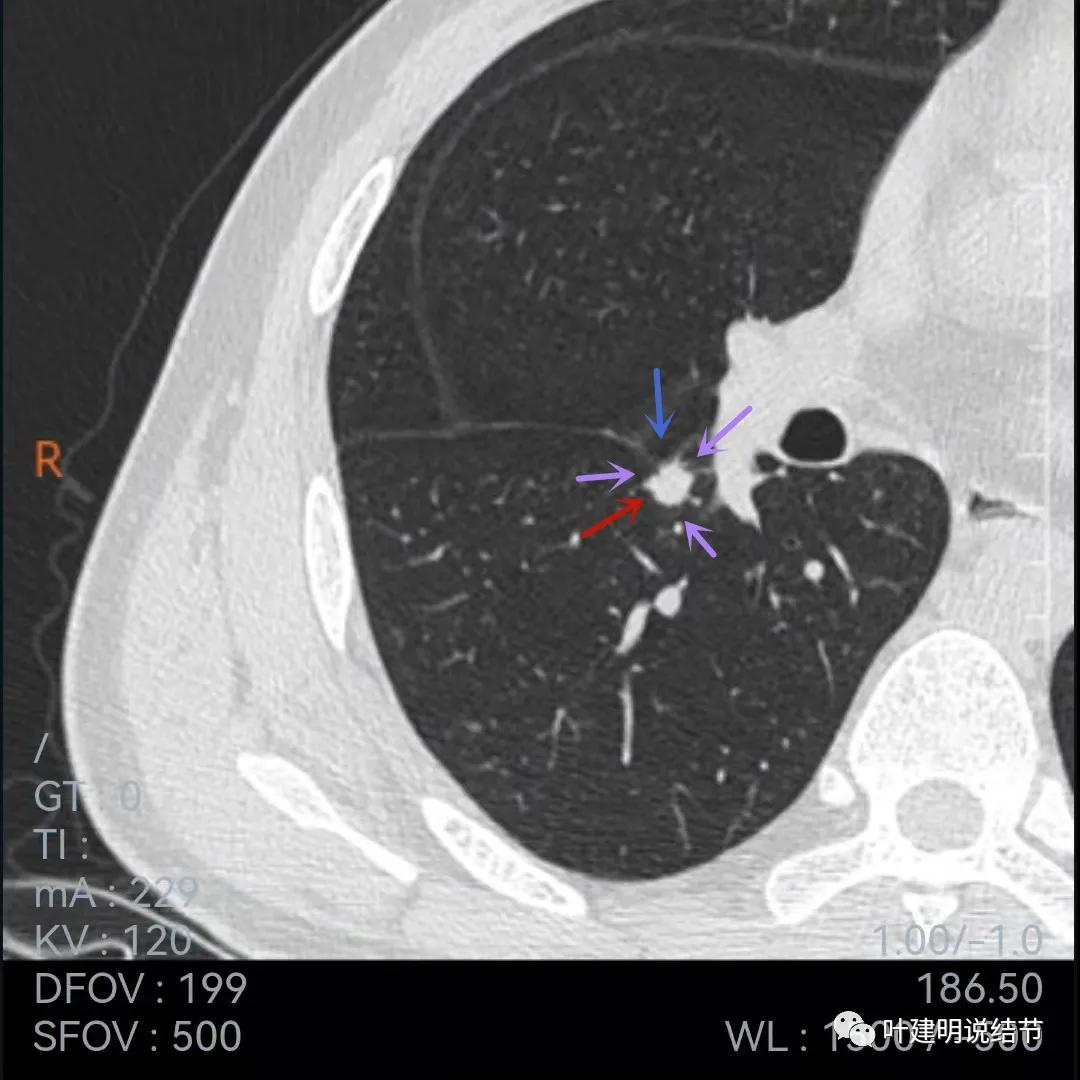

再来看当地医院的靶扫描:

病灶叶间胸膜凹陷,有细毛刺(紫色箭头),但毛刺与病灶大小相比感觉长了点

中间密度还是略低(黄色箭头),胸膜牵拉仍明显(蓝色箭头)

细毛刺(紫色)、胸膜凹陷(蓝色)以及中间偏低密度(黄色)

上图棘突样征象较明显(紫色箭头)